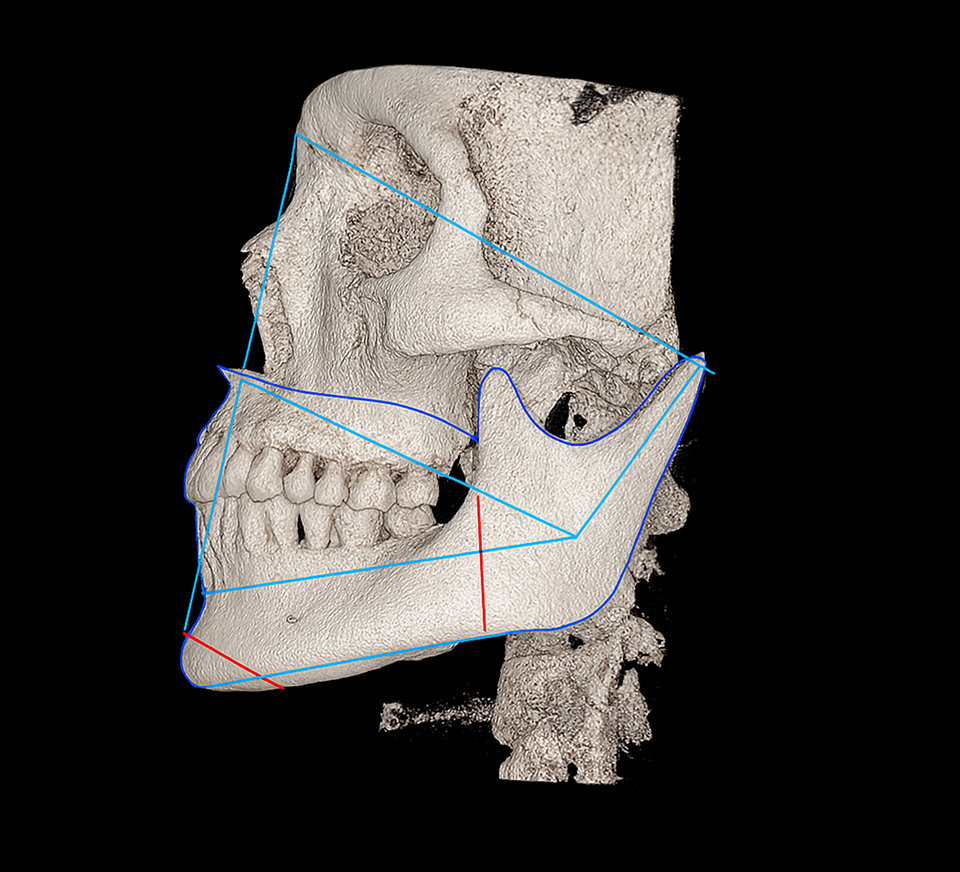

서울오브치과병원은

인체에 유해한 금속 성분을 사용하지 않으며,

환자의 구강 상태와 치료 목적을 면밀히 고려해

장기적으로 안전하고 기능적인 보철물만을 선택합니다.